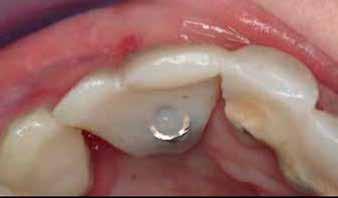

Facial-palatal width was determined to be adequate for implant placement of 3.0mm and 3.5mm implant diameters for the lateral and central incisors, respectively. The plan was to place the implants to the cortical base of the nasal floor and utilize the fixtures and healing abutments as “tent poles” to support the same composite bone graft used in the first procedure (Fig. 9).

Figure 9: Implant insertion prior to additional bone grafting. Implants were purposely not over-seated, to facilitate restorative treatment and avoid hygienic challenges after restoration.

Figure 10: Additional bone grafting, utilizing the same composite graft of rhBMP-2/ACS & FDBA was performed to cover the supracrestal threads of both implants. Short (2.0mm) healing abutments, rather than cover screws, were utilized to support the overlying flaps and achieve maximum vertical regeneration

A large portion of the osteoinductive ACS was applied over the graft and 2.0mm tall healing abutments (Fig. 10), then an amnion- chorion membrane (BioXclude; Snoasis) was applied crestally to aid in soft tissue maturation (Fig. 11)